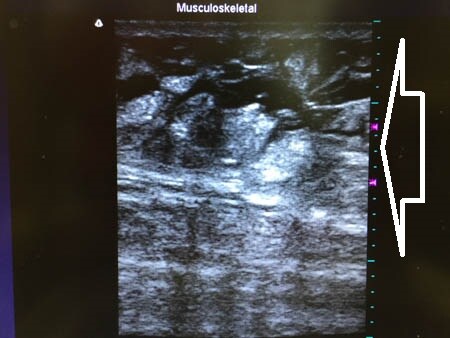

左太もも後面。